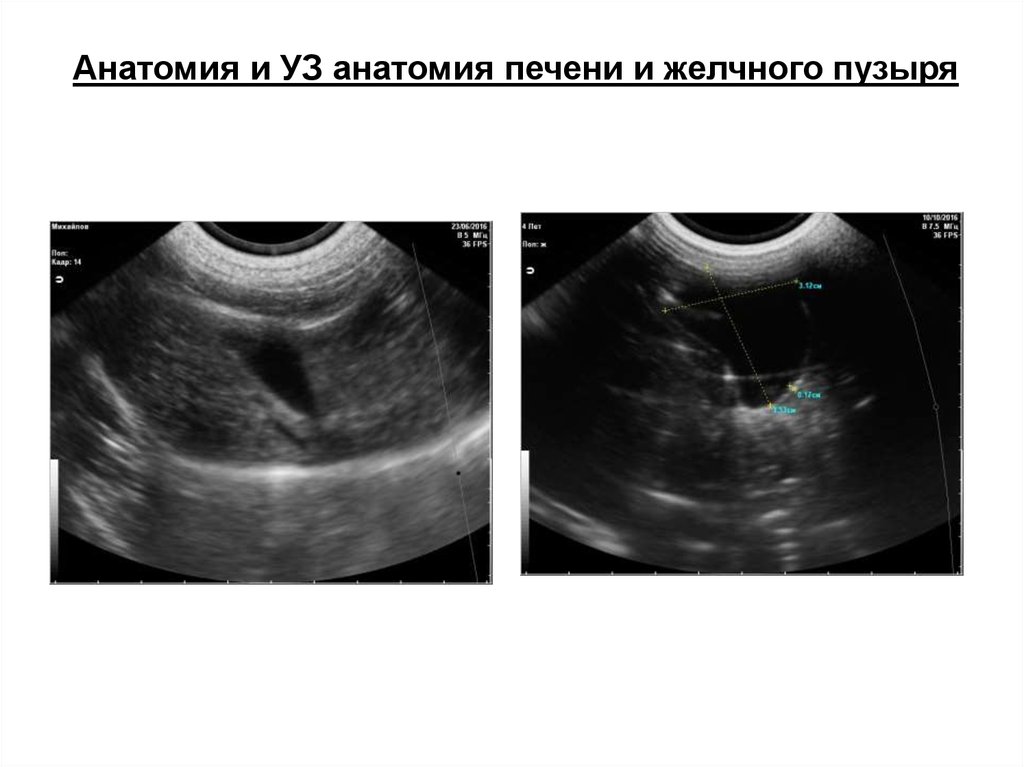

Анатомия и УЗ анатомия печени и желчного пузыря

Серповидная связка